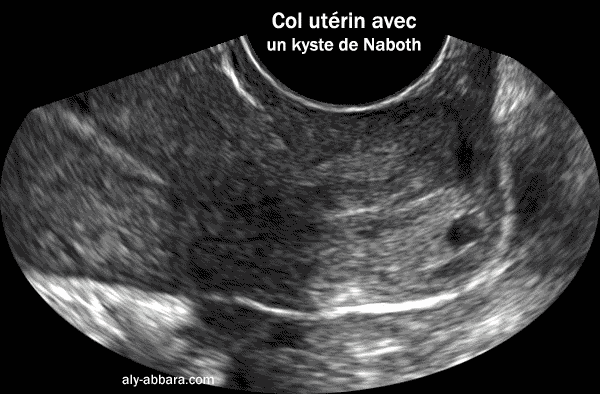

- Le kyste

de Naboth :

- Connu

aussi sous le nom de follicule de Naboth, de kyste glandulaire

ou de kyste de rétention ; il se forme sous la surface épithélial

du col utérin lorsque l'orifice d'une crypte glandulaire endocervicale

est obstrué par l'épithélium cylindrique métaplasique,

l'épithélium glandulaire cylindrique reste actif à

l'intérieur de la crypte obstruée et il sécrète

du mucus qui dilate la glande et lui donne l'aspect kystique (ou folliculaire)

de taille variable

Ces kystes glandulaires rétentionnels sont visibles sur l'exocol,

mais paroi ils sont situés profondément dans

le col ,

près du canal endocervical et invisibles à l'observation

du col par le spéculum ou le colposcope.